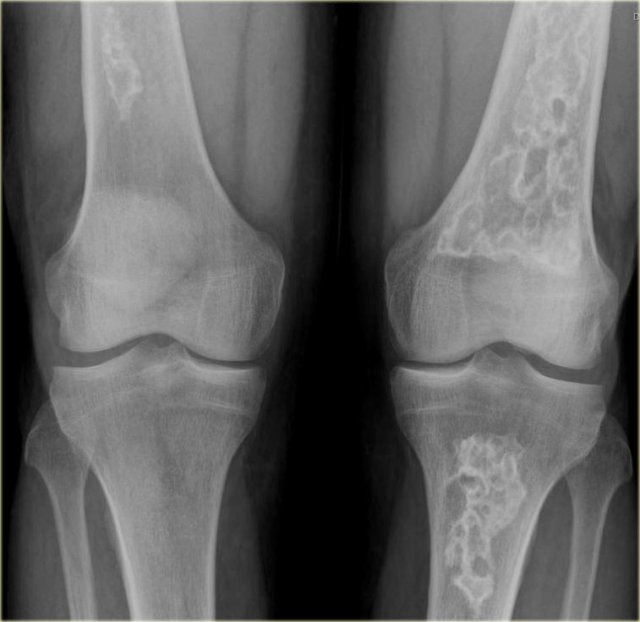

A sclerotic lesion is typically diagnosed using radiographic imaging. The most common type of radiographic imaging used to diagnose a sclerotic lesion is a plain film x-ray. However, other modalities such as computed tomography (CT) and magnetic resonance imaging (MRI) may also be used.

When a sclerotic lesion is seen on a plain film x-ray, it appears as a radiodense area. The borders of the lesion may be well-defined or ill-defined. The size of the lesion can vary from a few millimeters to several centimeters.

If the diagnosis is uncertain based on plain film x-ray, CT or MRI may be ordered. These modalities can provide more information about the size, shape, and exact location of the lesion.